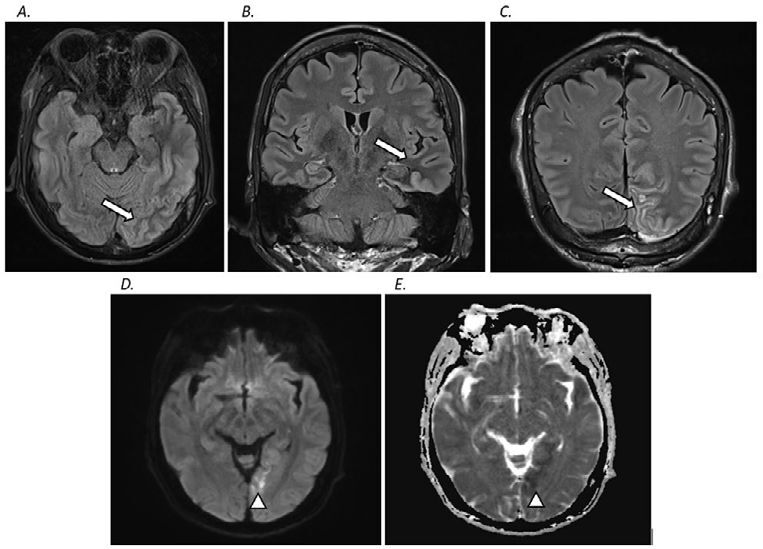

Neurological manifestations of nonketotic hyperglycemia are frequently seen, with mainly symptoms of confusion or coma. While hyperglycemia-induced seizures are less common, isolated aphasic status epilepticus is very rare, difficult to diagnose, and may be unrecognized by clinicians. In this case report, a 51-year-old man who presented with confusion and incoherent speech for two weeks is discussed. He was diagnosed with nonketotic hyperglycemia, whose electroencephalography (EEG) findings were suggestive of isolated aphasic status epilepticus. His magnetic resonance imaging (MRI) of the brain showed subcortical T2/FLAIR hypointense lesions with cortical T2/FLAIR hyperintensities and restricted diffusion. Although this condition usually responds well to intensive insulin therapy and fluid replacement, many researchers found some persistent aphasic seizures that did not improve until the addition of anti-seizure medications (ASMs).